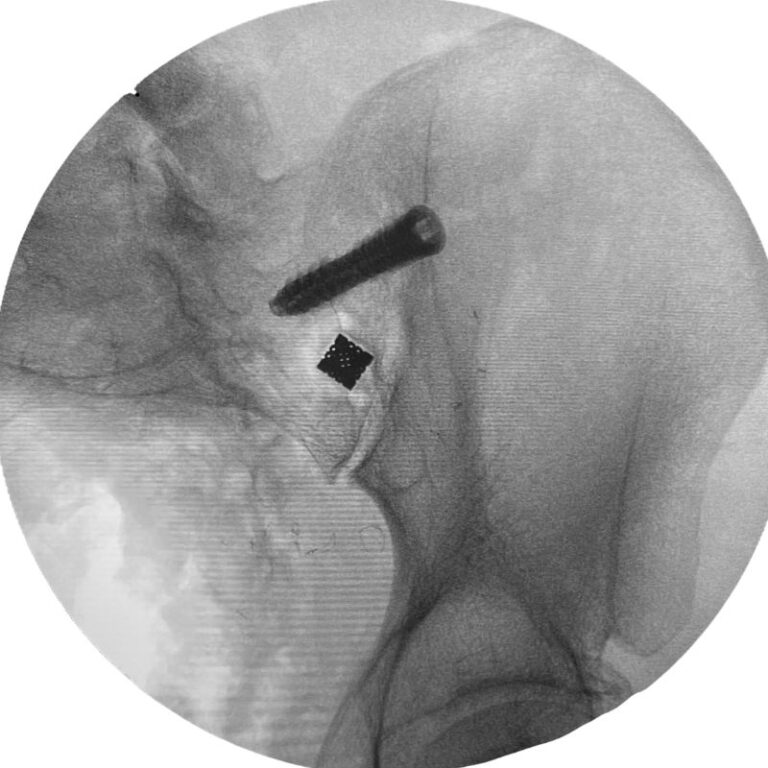

Step 2: Lateral Oblique Compression Screw Insertion

A TransLoc 3D™ screw is placed using a lateral oblique approach, compressing the joint onto the intra-articular implant.